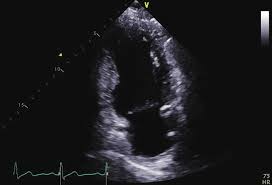

Parasternal Short Axis (PSAX)

This "donut-shaped" Echo view at the papillary muscle level is the gold standard for evaluating all three major coronary territories simultaneously

Anteroseptal and Inferolateral

LAD

Anterior and Inferior